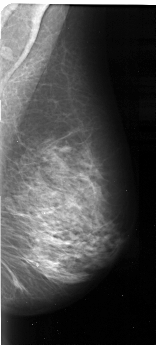

A_1097_1.RIGHT_MLO

RIGHT_MLO LINES 5161 PIXELS_PER_LINE 2326 BITS_PER_PIXEL 16 RESOLUTION 42 NON_OVERLAY